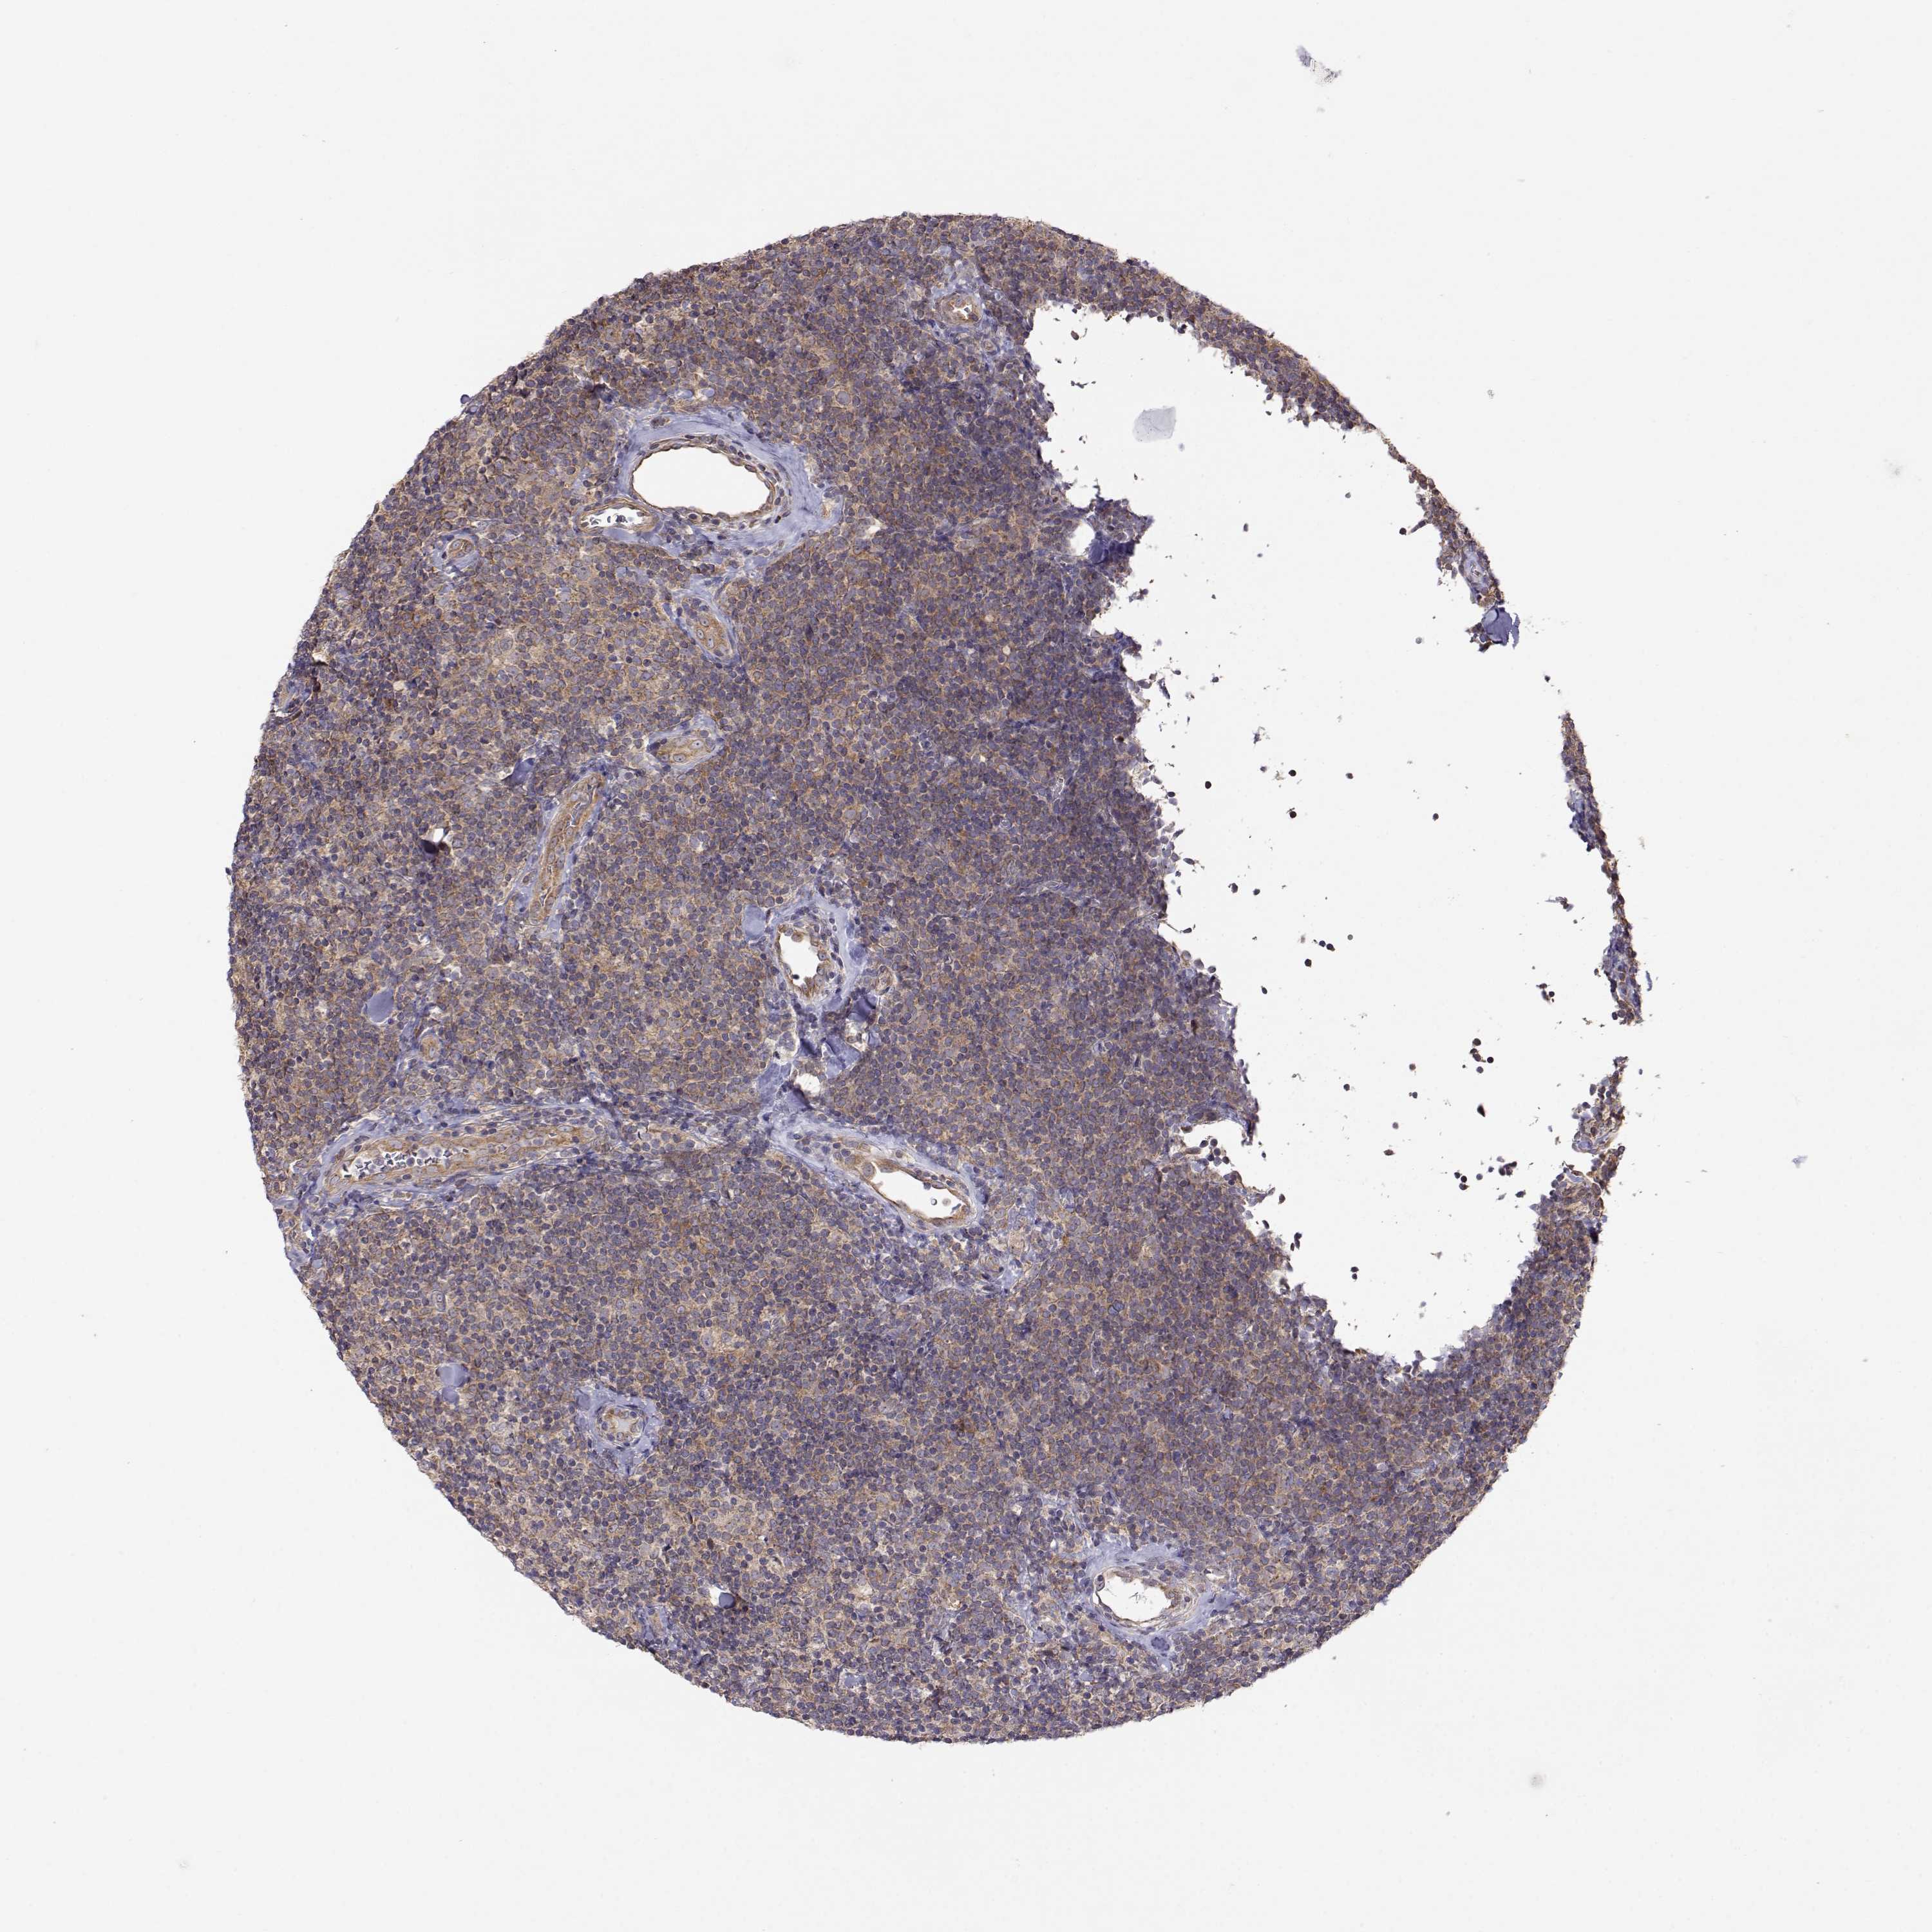

LYMPHOMA - Protein expressioni

A mouse-over function shows sample information and annotation data. Click on an image to view it in a full screen mode. Samples can be filtered based on level of antibody staining by selecting one or several of the following categories: high, medium, low and not detected. The assay and annotation is described here.

Antibody stainingi

Antibody staining in the annotated cell types in the current human tissue is reported as not detected, low, medium, or high, based on conventional immunohistochemistry profiling in selected tissues. This score is based on the combination of the staining intensity and fraction of stained cells.

Each image is clickable and will lead to virtual microscopy that enables deeper exploration of all samples and also displays staining intensity scores, fraction scores and subcellular localization as well as patient and tissue information for each sample.

Antibody HPA073653

Staining

High

Medium

Low

Not detected

Intensity

Strong

Moderate

Weak

Negative

Quantity

>75%

75%-25%

<25%

None

Location

Nuclear

Cytoplasmic/membranous

Cytoplasmic/membranous,nuclear

Malignant lymphoma, non-Hodgkin's type, Low grade

Malignant lymphoma, non-Hodgkin's type, High grade

Hodgkin's disease, NOS